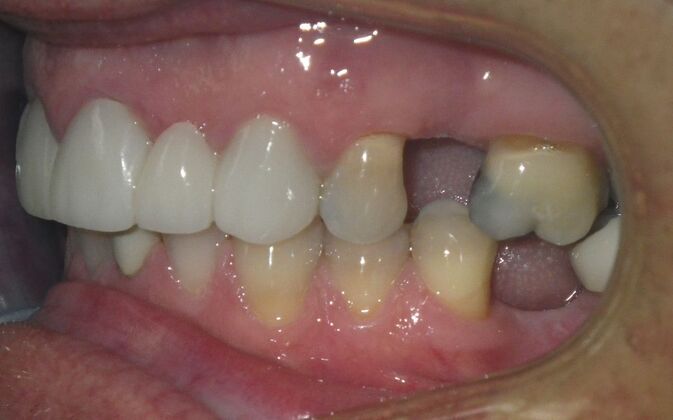

Cosmetic Changes with Veneers and Crown and Bridge: Case 5

Patient wanted to see about getting his upper front crowns replaced. He has had them for 35 plus years. Also concerns about his gums receding and the metal margins of crowns showing. Also talked with him about the need for crown lengthening which would have helped decrease the gummy smile; however, he chose not to do this. I thought just replacing the existing crowns to the existing gingival margins would be a great help. So the existing porcelain/metal crowns were removed and new all ceramic single unit crowns placed from upper right cuspid,lateral incisor and right central incisor. Then a 3-unit all ceramic bridge was placed from upper left central incisor to upper left cuspid. This patient and most of all his wife were very pleased with the end result.